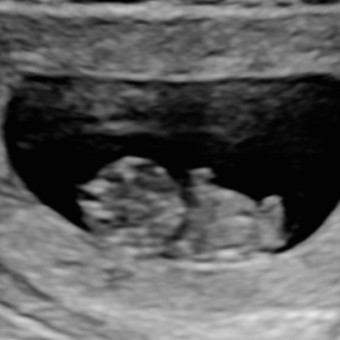

Gabriella Schiraldi & Elijah Sepulveda

September 9, 2026

Haii!! Thank you so much for blessing Elowyn 🥹